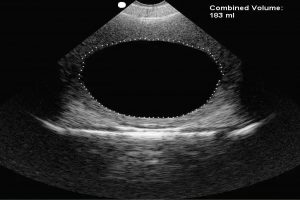

Diplomados en Ultrasonografía